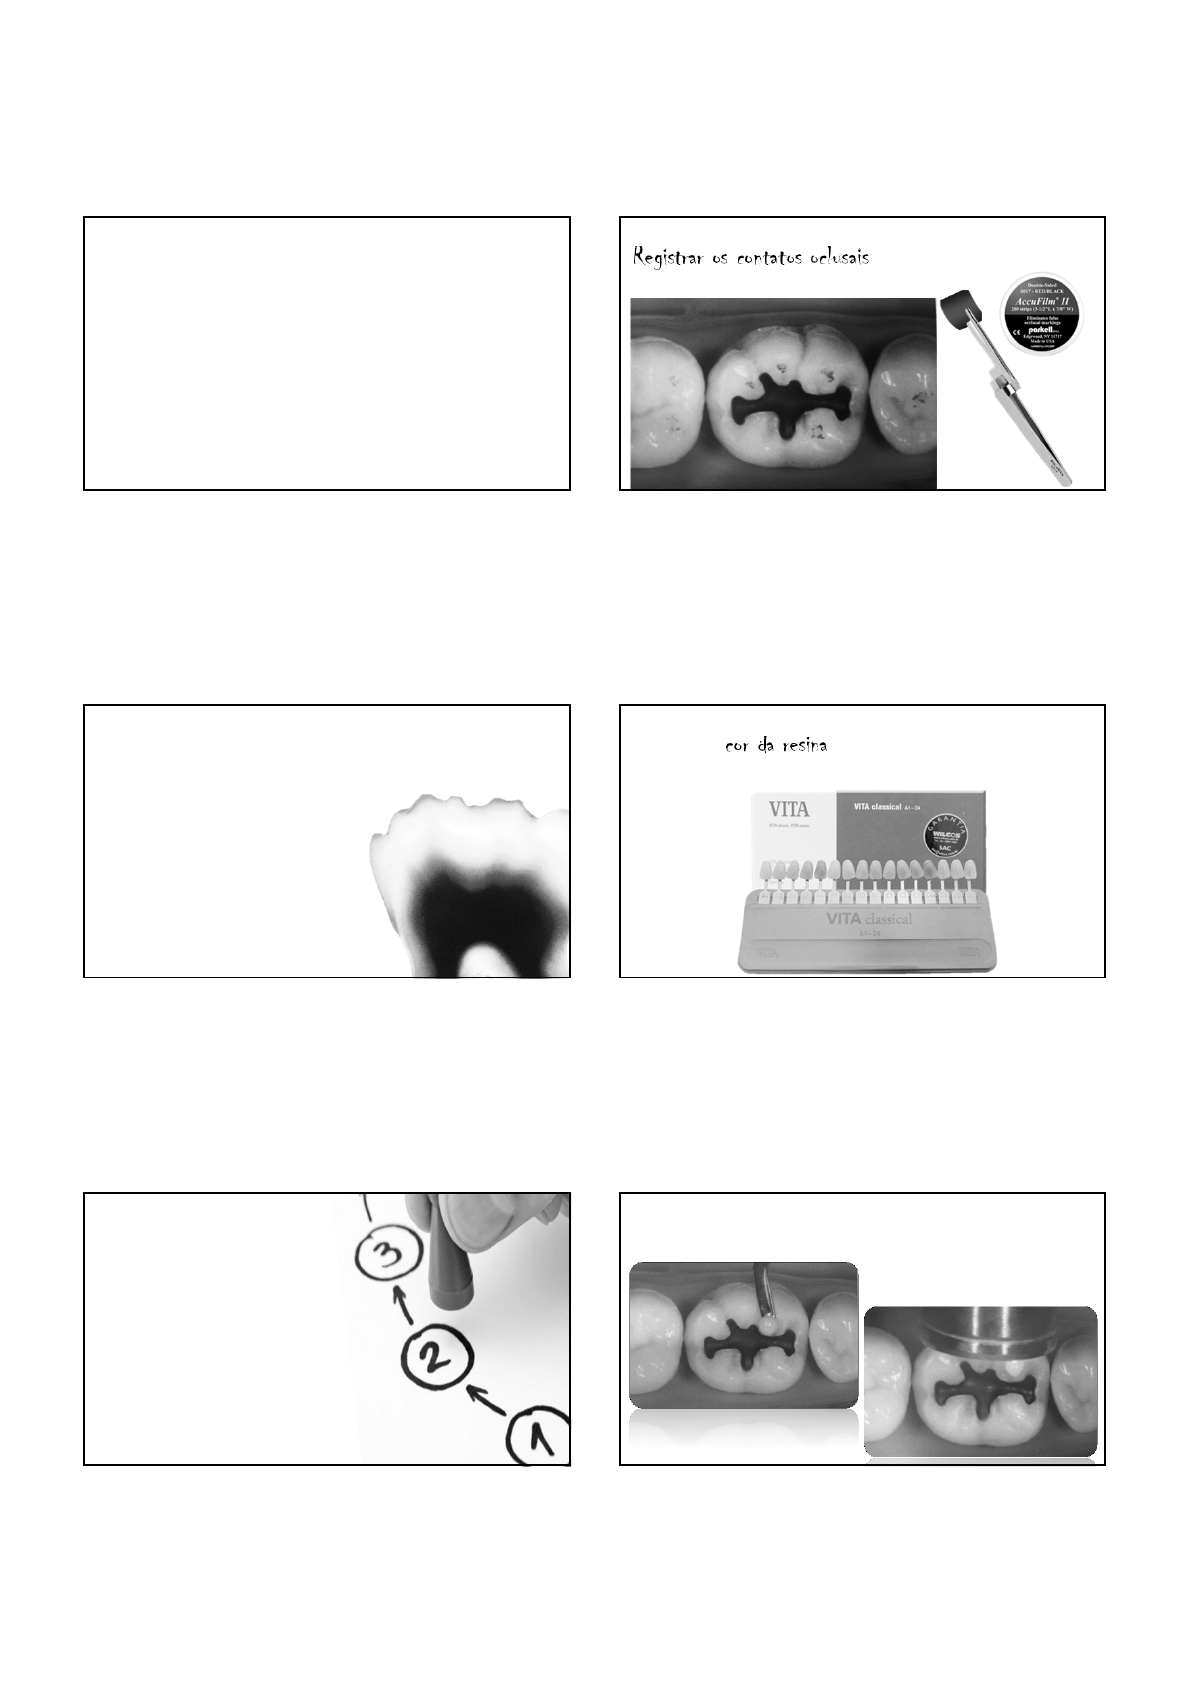

Registrar os contatos oclusais

Seleção de cor da resina